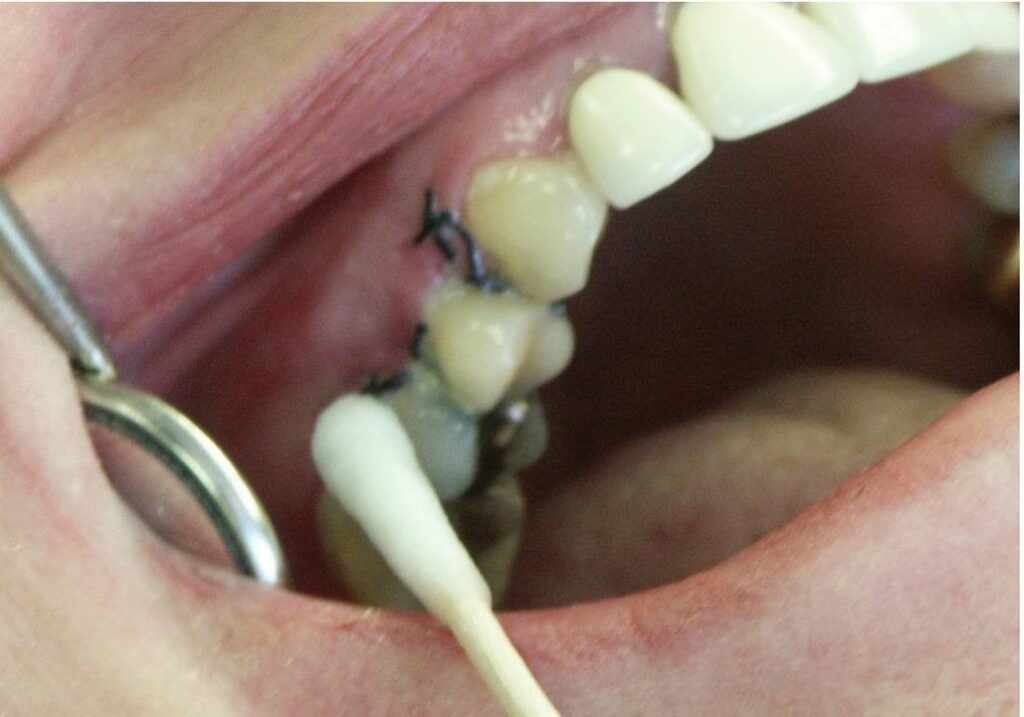

Sau khi tháo băng, sử dụng một đầu tăm bông, nhúng vào dung dịch súc miệng khử trùng pha loãng hoặc hydro peroxide để lau sạch thức ăn và mảnh vụn vi khuẩn, như trong hình 34.1